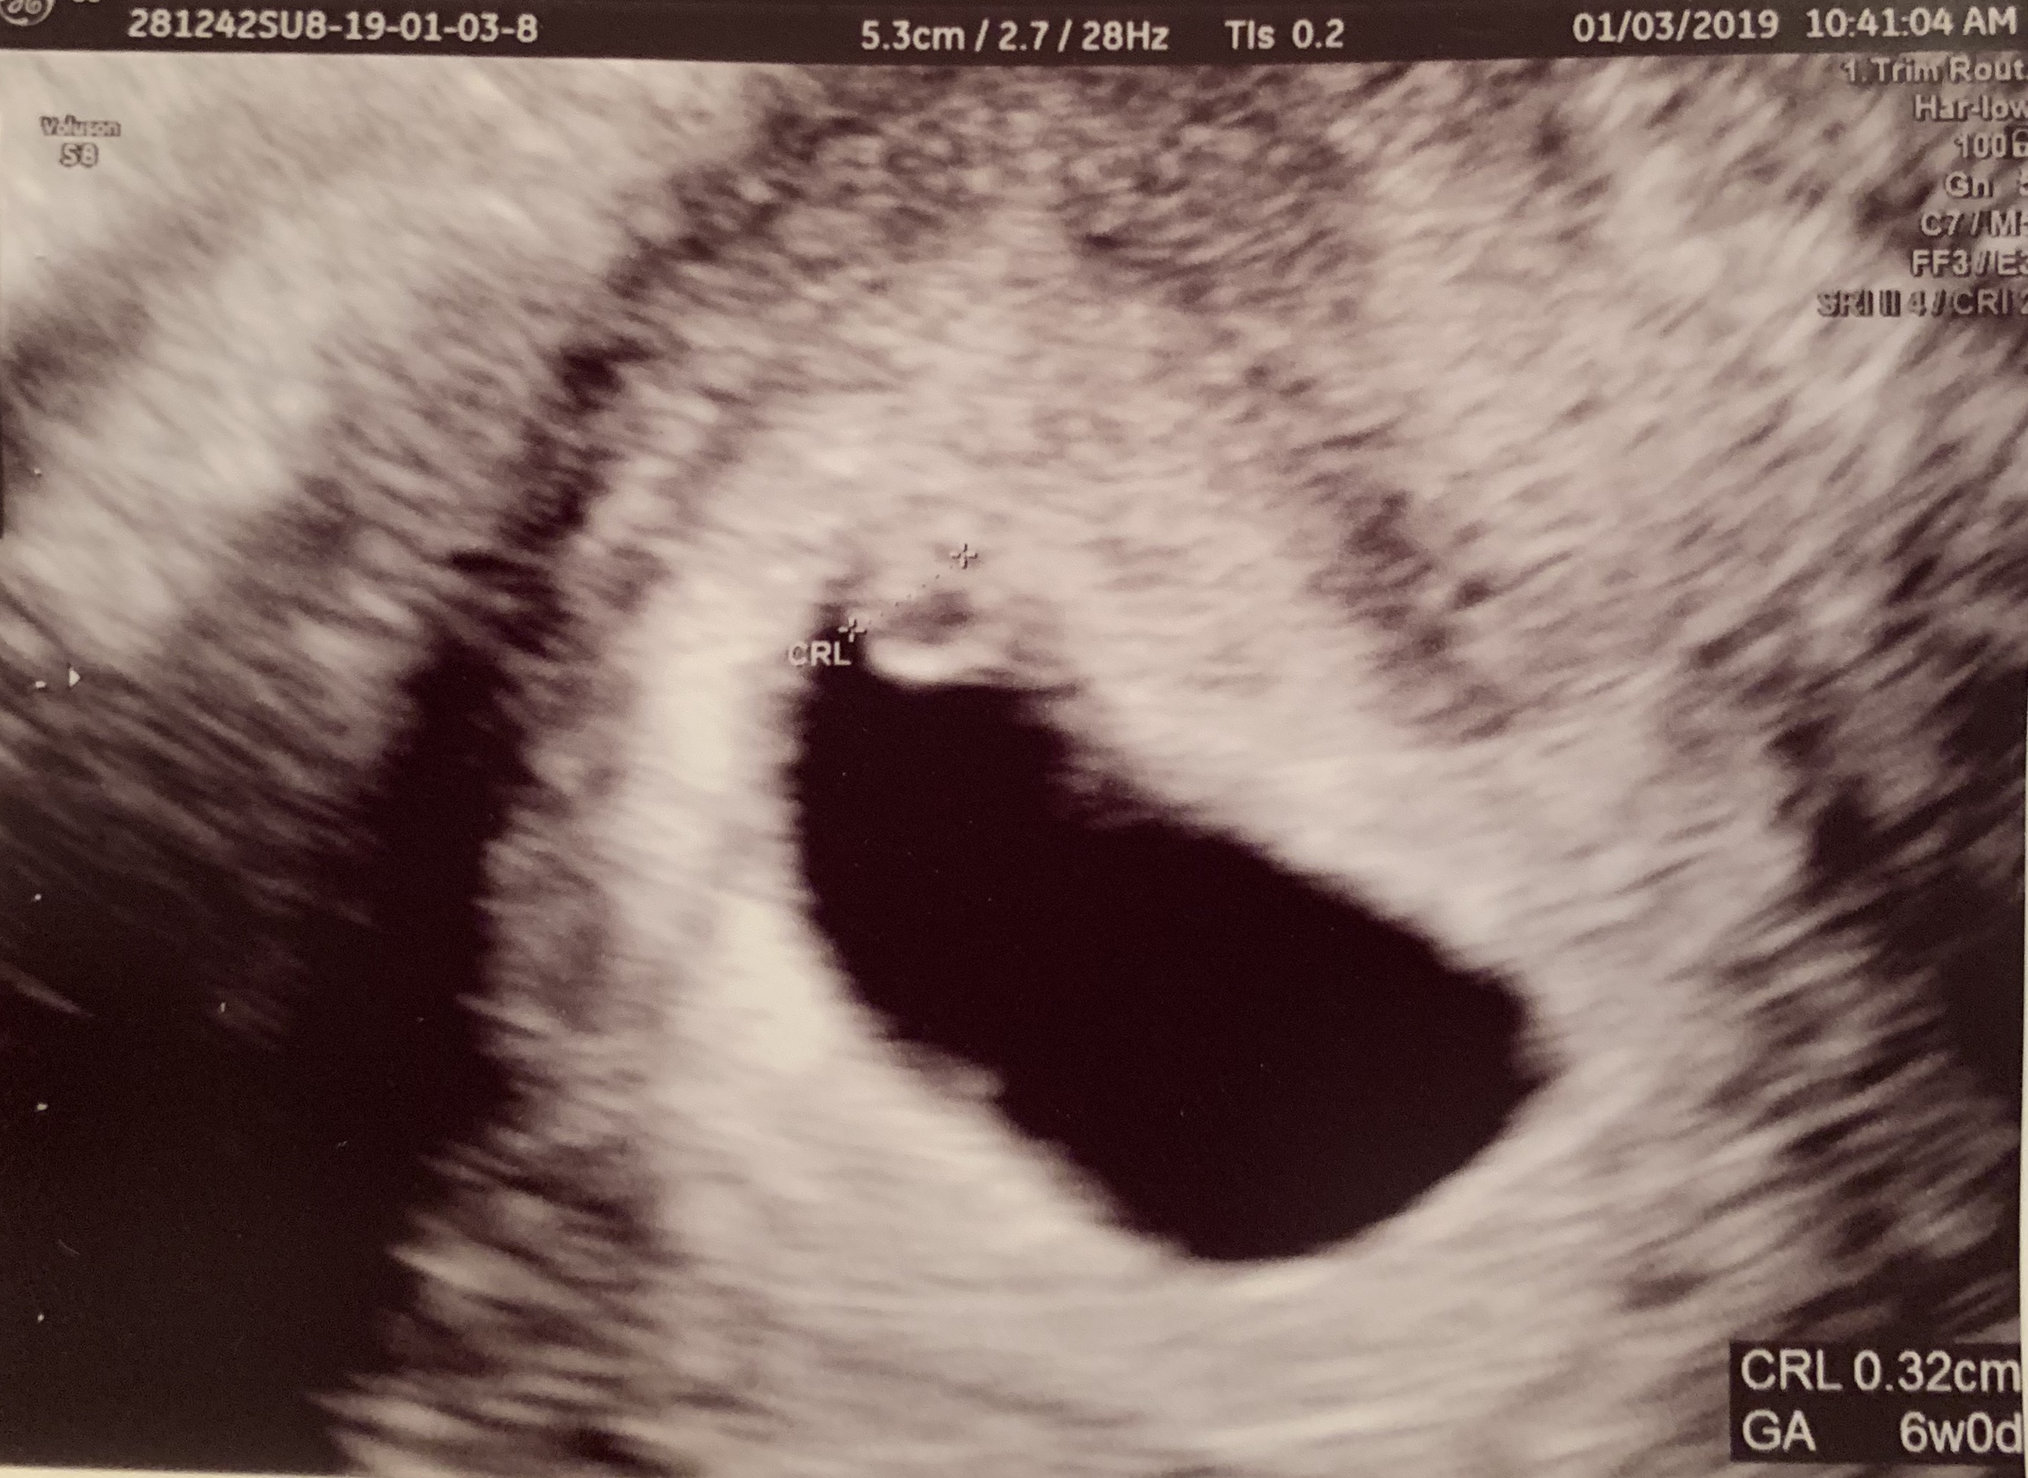

Had our first confirmation US yesterday morning. We were guestimating closer to seven weeks, but babe measured at 6w0d. We couldn't hear the heartbeat, but we could see flutters. We go back in three weeks for another US to confirm everything is progressing normally.